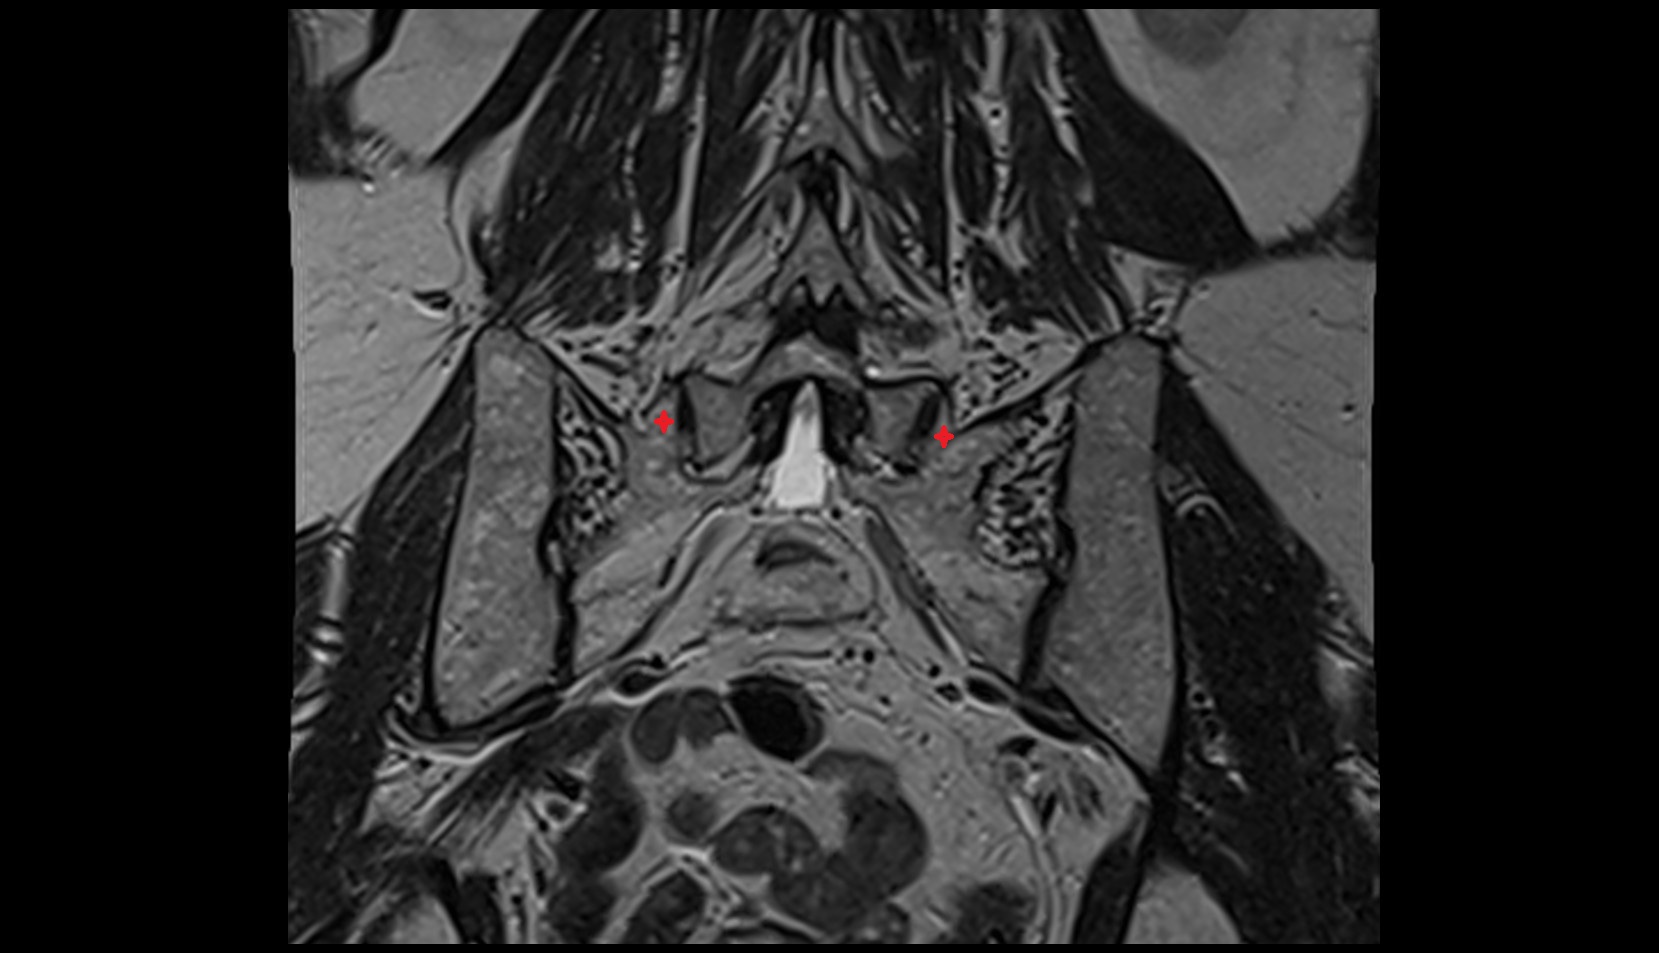

- Sacroiliac joint